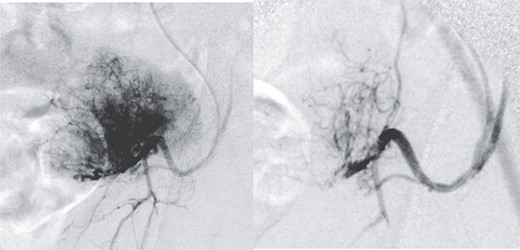

Radical surgery was decided after discussion in the tumors multidisciplinary committee, and previous vascular embolization was proposed to reduce the potential risk of bleeding (Fig. 2).

Presurgical tumor embolization. (A) By contralateral approach, left femoral diagnostic angiography is performed, showing hypervascular tumor pattern depending on the left epigastric artery. (B) Control after embolization of the two medial thirds of the tumor with calibrated particles of 600 +/− 75 microns. The rest of the tumor cannot be safely embolized due to the existence of obturator branches.